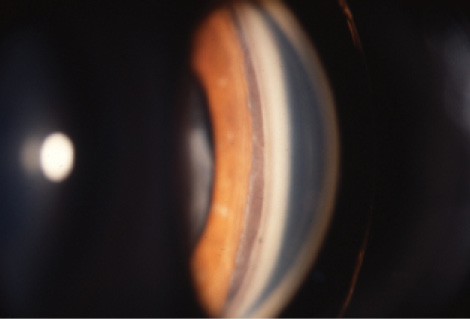

Hyphema is a frequent presenting sign after ocular trauma.12 Initially, there may only be a microscopic hyphema, characterized by red blood cells floating in the aqueous. In later stages, these cells can settle into a layered hyphema (Figure 4). In many cases, with conservative management, the blood clears without intervention in a few days, but bleeding may recur, especially in the first few weeks after injury.13

Figure 4. A layered hyphema with corneal blood staining at the slit lamp.